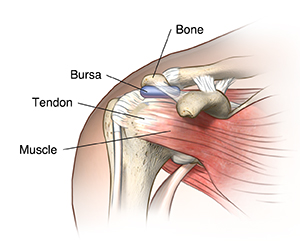

Bursitis is the inflammation of a bursa. A bursa is a closed, fluid-filled sac. It works as a cushion and gliding surface to reduce friction between tissues of the body. The major bursae (this is the plural of bursa) are located next to the tendons near the large joints, such as the shoulders, elbows, hips, and knees.

Bursitis is inflammation of a bursa. This fluid-filled sac works as a cushion and gliding surface to reduce friction between tissues of the body.